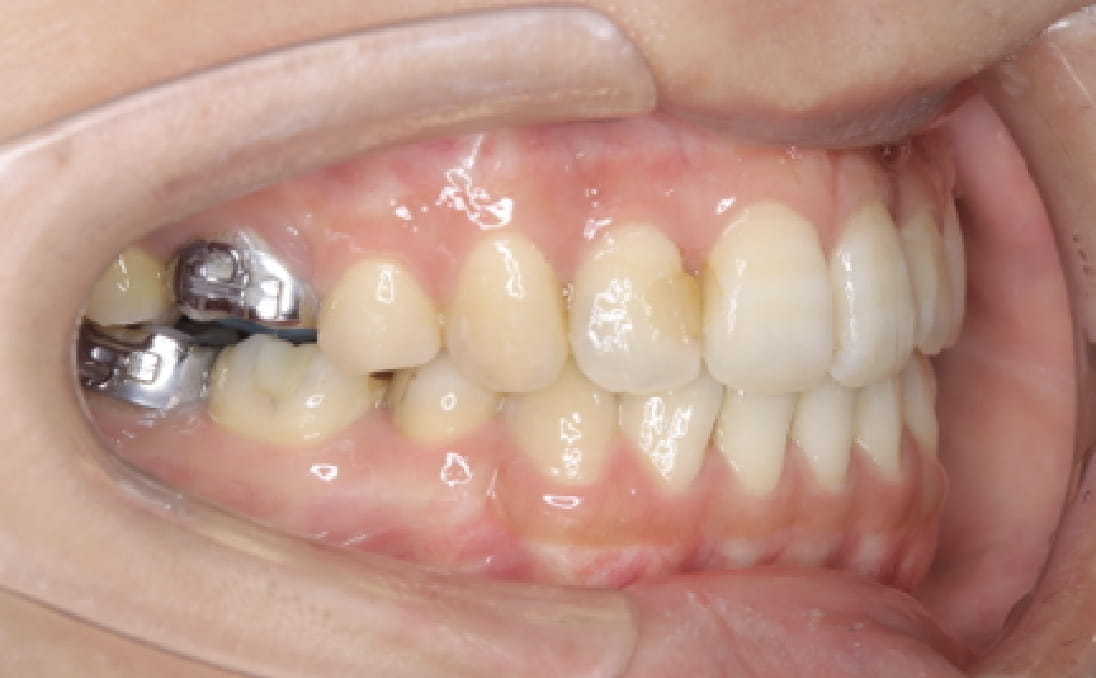

《上下顎前突》

症例

主訴 口ゴボが気になる

治療装置 ハーフリンガル矯正(上顎裏側・下顎表側)

抜歯 抜歯あり

診断名 上下顎前突(口ゴボ)

副作用 歯肉退縮・歯根吸収・歯髄・壊死・癒着による予期せぬ歯の動き

上下顎ともに裏側で装置を完全に隠しながら、アンカースクリューで前歯をしっかり後退。見た目と仕上がりを両立した症例。

治療前

治療中①

治療中②